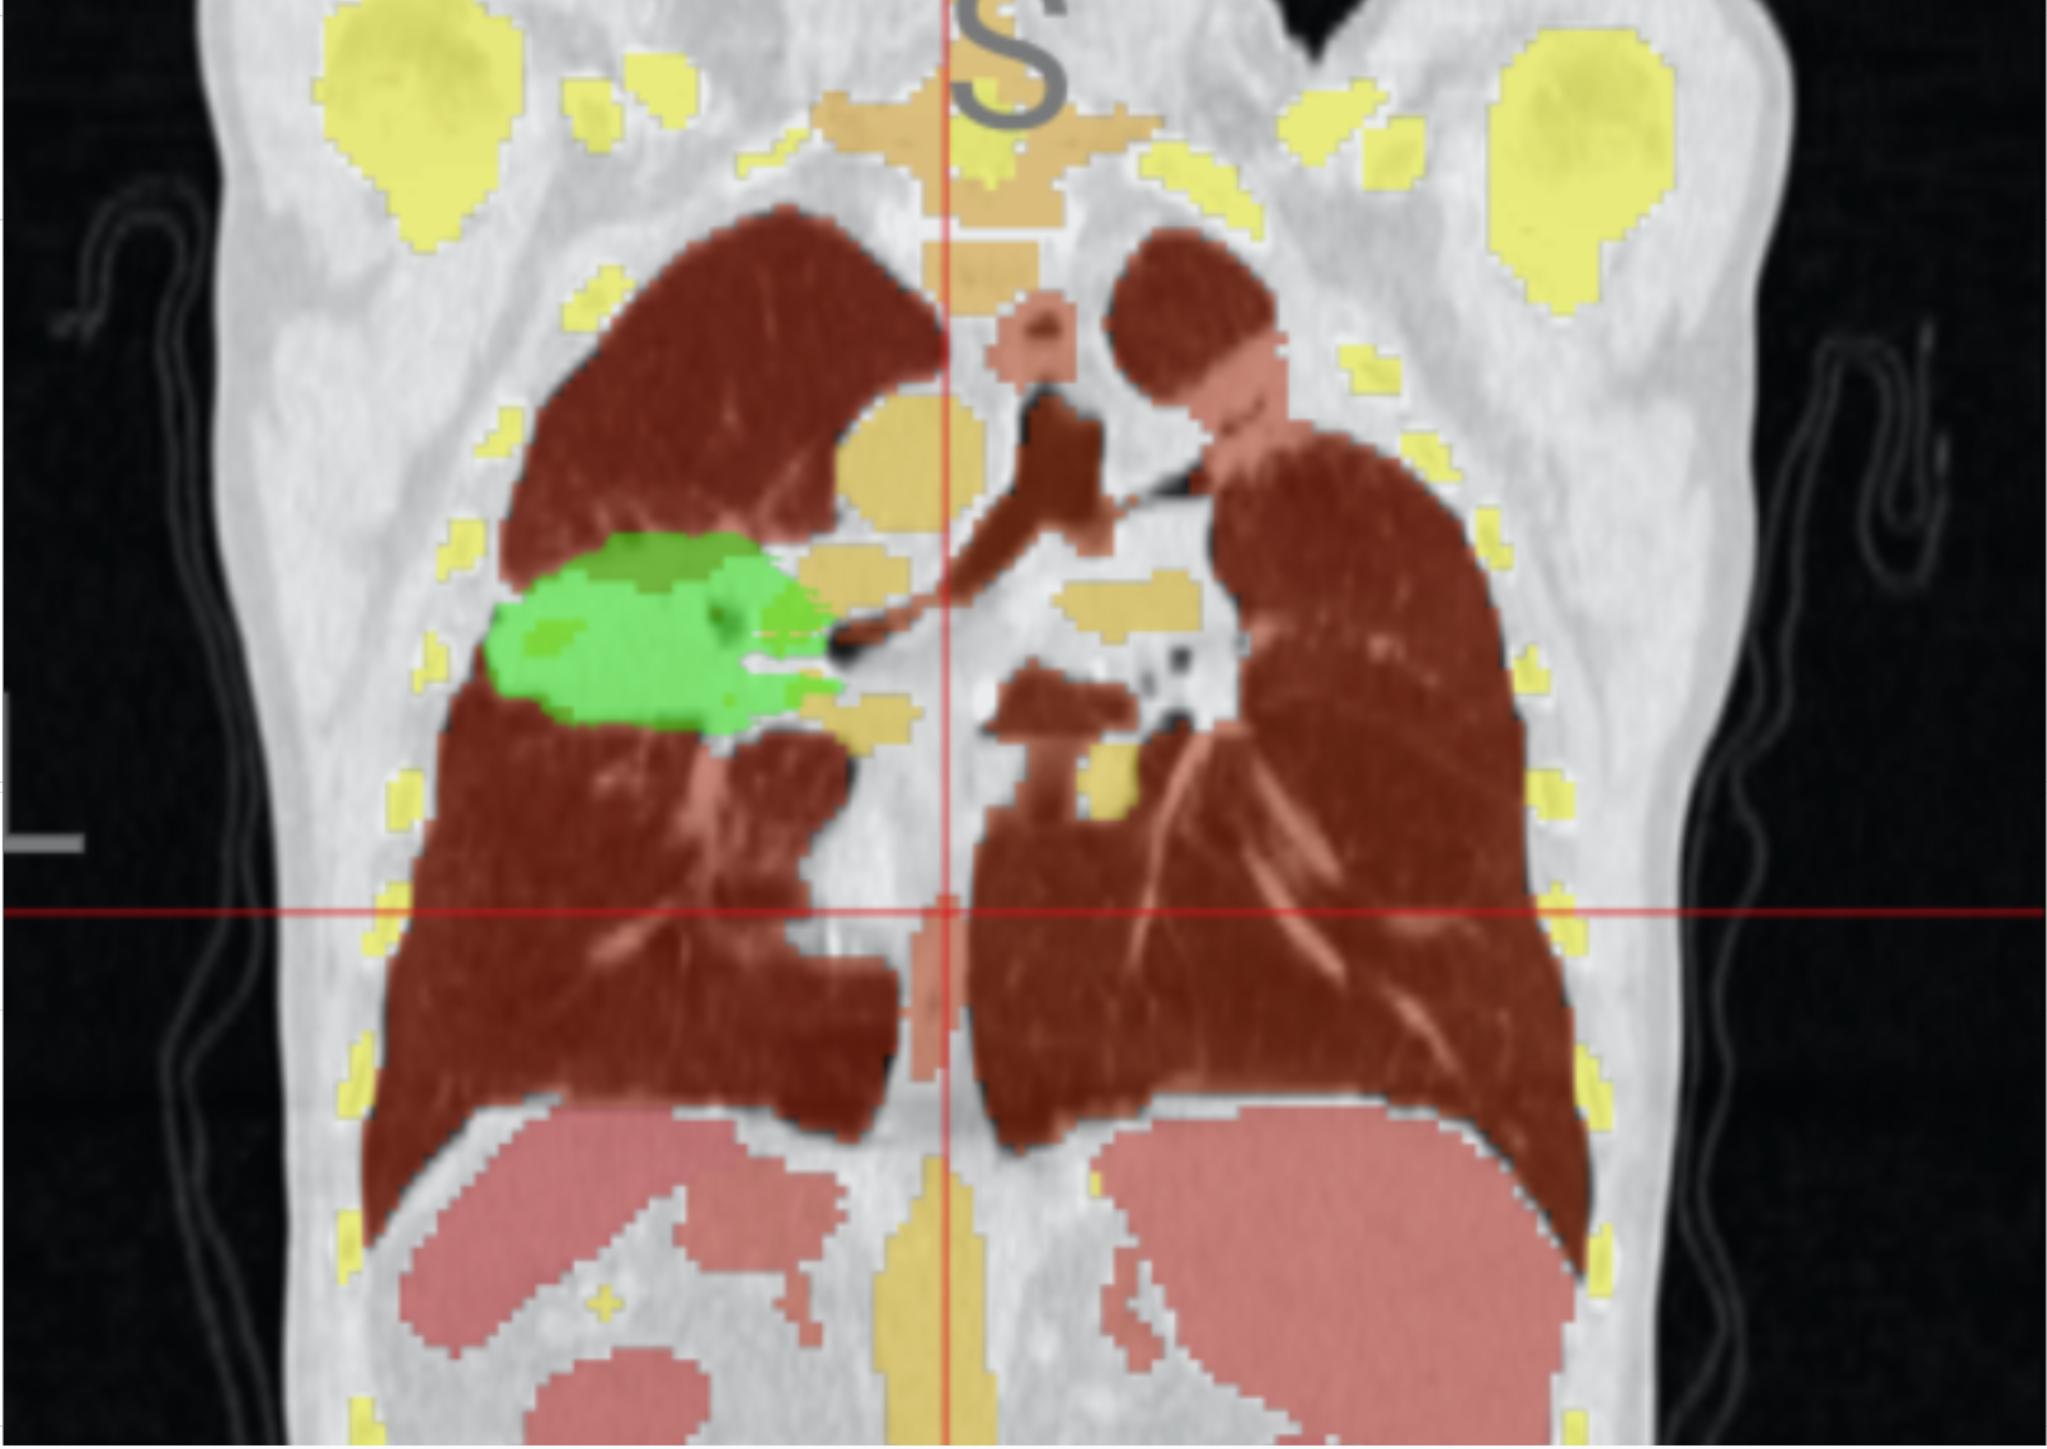

Segmentation overlay

Bias and confounder mitigation for image diagnosis, plus physiologically plausible augmentation from lung motion simulation.

Integrating Mechanistic Knowledge into Deep Learning for Improved Cancer Detection